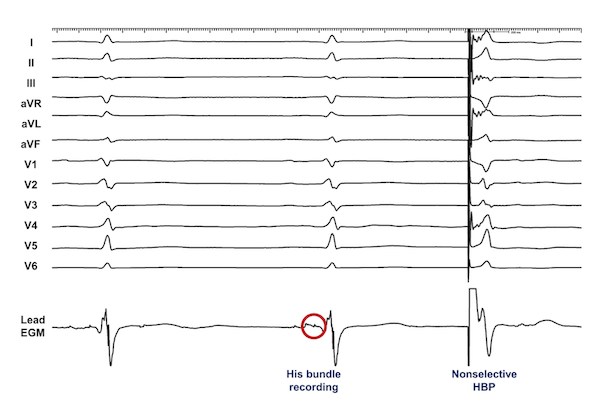

The criteria for assessing conduction system capture for patients undergoing His bundle pacing (HBP) have now been established.14 Particularly among patients with narrow QRS at baseline, the template for assessing conduction system capture is the patient’s intrinsic QRS. In patients undergoing HBP for CSP, the goal is to reproduce this QRS as closely as possible across all 12 leads of the standard surface ECG. Selective capture is present when an identical QRS or near-identical is inscribed with an isoelectric segment present between the stimulation artifact and the QRS onset in all 12 leads (Figure 1). Nonselective capture is present when there is a “pseudo-delta” or slurred upstroke beginning at the stimulation artifact in at least one lead (Figure 2). Critical in patients undergoing HBP is that output-dependent morphology (ODM) changes should be present, which allow implanters to distinguish between nonselective HBP and RV septal capture.15,16 There may be a small cohort of patients in whom ODM changes are not present with HBP, and use of pacing maneuvers may be helpful to help distinguish morphologic differences in this setting.17,18

Selective LBBP may be distinguished from LVSP since an isoelectric segment will be present in all 12 leads (Figures 3-4). Similar to HBP, nonselective LBBP will also have a right bundaloid configuration in V1 with a pseudo-delta apparent in multiple leads (Figure 5). In the case of nonselective LBBP, then, adjacent LV septal capture is present along with LCS capture. LCS capture may be assessed at implant through observation of an LBB or Purkinje potential at the lead tip during implant, although the presence of a potential does not necessarily mean it will be captured. The interval between the potential to the QRS onset should then also be similar to the width of the isoelectric segment in selective LBBP.